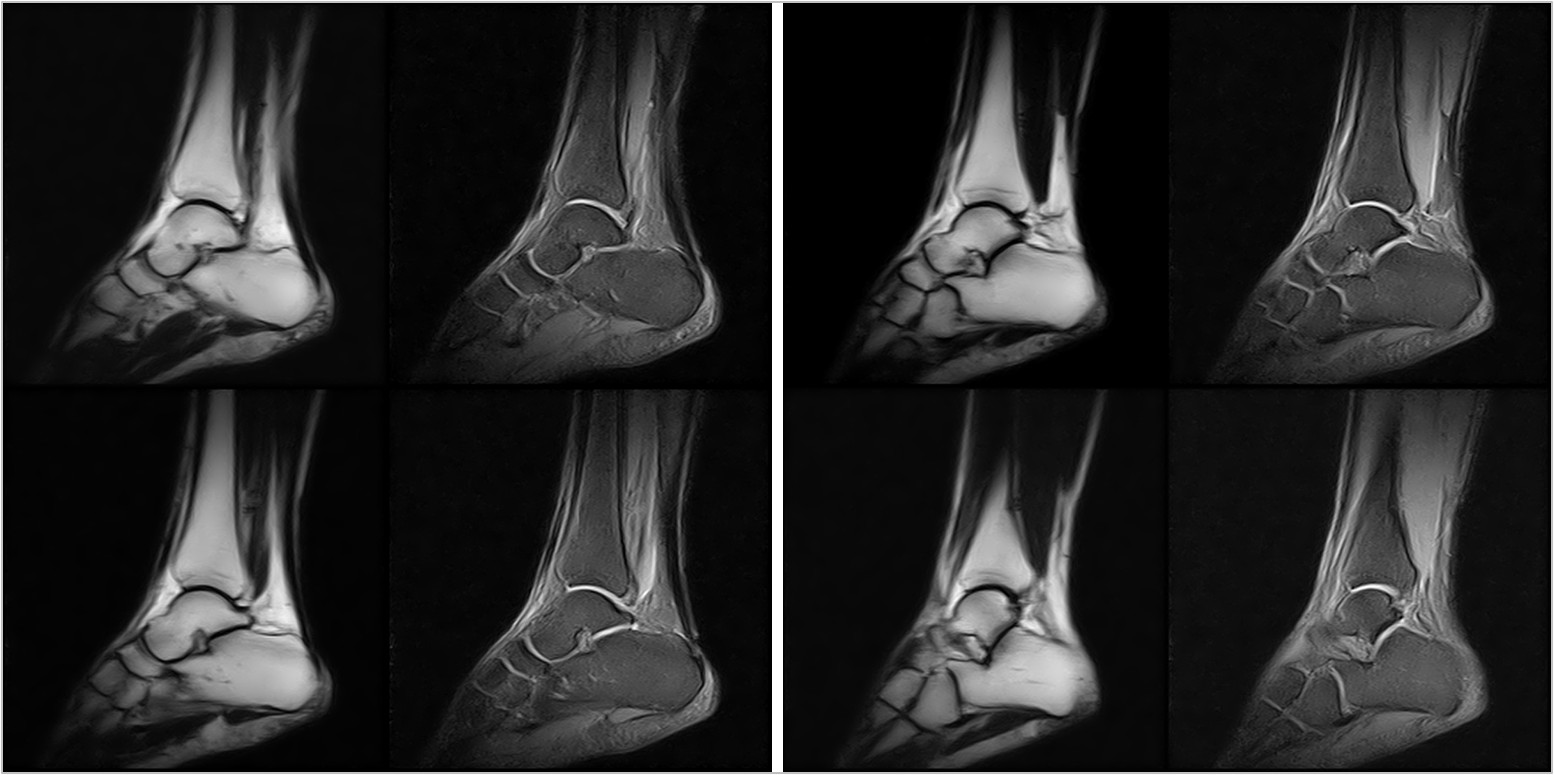

Hình ảnh lâm sàng

Giải pháp lâm sàng ấn tượng